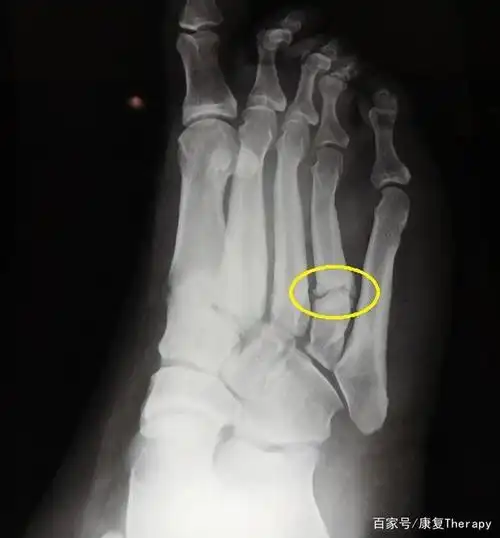

走这么多路,不怕骨折吗?医生提醒,走路脚疼要小心是骨折